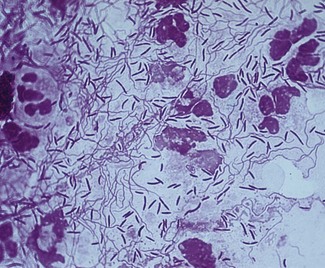

Gram-negative, strictly anaerobic, cigar-shaped bacilli with pointed ends (Fig. 18.1). Cells often have a central swelling. A Gram-stained smear of deep gingival debris obtained from a lesion of acute ulcerative gingivitis is a simple method of demonstrating the characteristic fusobacteria, together with spirochaetes and polymorphonuclear leukocytes (Fig. 18.2). These, together with the clinical picture, confirm a clinical diagnosis of acute ulcerative gingivitis.

Fig. 18.1 A photomicrograph of fusobacteria showing characteristic Gram-negative, cigar-shaped cells with pointed ends.